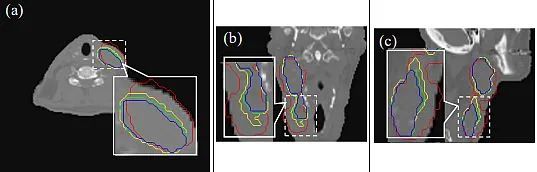

基于轮廓的图像配准

这种方法利用强烈的统计特性来匹配图像特征点。使用彩色图像分割提取图像中的感兴趣区域。

为了生成图像的轮廓——计算给定颜色集合的平均值。在分割过程中,图像中的每个RGB像素被归类为属于特定颜色范围或不属于。此外,使用欧几里得距离来确定相似度。

这两组图像被编码为二值图像(黑白)。使用高斯滤波器来消除噪声,因为阈值会导致图像模糊。接着获取图像的轮廓。轮廓方法的准确性令人满意,但缺点是手动操作且速度慢。

医学图像配准旨在找到最佳的空间变换,以最佳地对齐现有的解剖结构。它被广泛应用于许多临床应用中,例如图像重建、图像引导、运动跟踪、分割、剂量积累等。医学图像配准是一个宽泛的主题,可以从不同的角度来考虑。

从输入图像的角度来看,配准方法可以分为单模态、多模态、跨患者和同患者配准。从变形模型的角度来看,配准方法可以分为刚性、仿射和可变形方法。从感兴趣区域(ROI)的角度来看,配准方法可以根据解剖部位分组,例如大脑、肺部配准等。